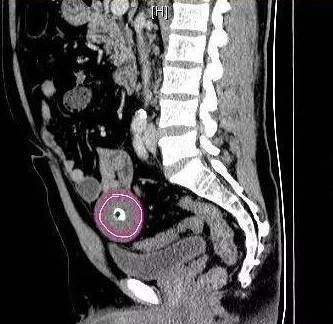

胡师傅说,他今年43岁,在崇阳一家水泥厂上班,家中有两个孩子,都在上学。前几天,他感觉头很疼,脑袋靠近右耳的地方像长了东西一样。到了5日晚上,他实在忍不住疼痛,来到崇阳县人民医院检查。“罕见!”接诊的医生检查后,也没有发现异样,血压什么的都正常。医生建议拍片看一看,CT片子拍出来了,医生一看吓了一跳:胡师傅右额颅内有根钉子,长达48毫米。

医生将检查结果告诉胡师傅,胡师傅听到后也十分诧异,“脑袋里怎么会有钉子,我自己怎么不知道?”胡师傅说,他的工作是看监控,完全不会接触到钉子。记者7日来到崇阳县人民医院,医生证实确有此事,他们已建议胡师傅到武汉的大医院进行手术治疗。7日上午,胡师傅已经与武汉一家医院联系好,准备节后到武汉手术。